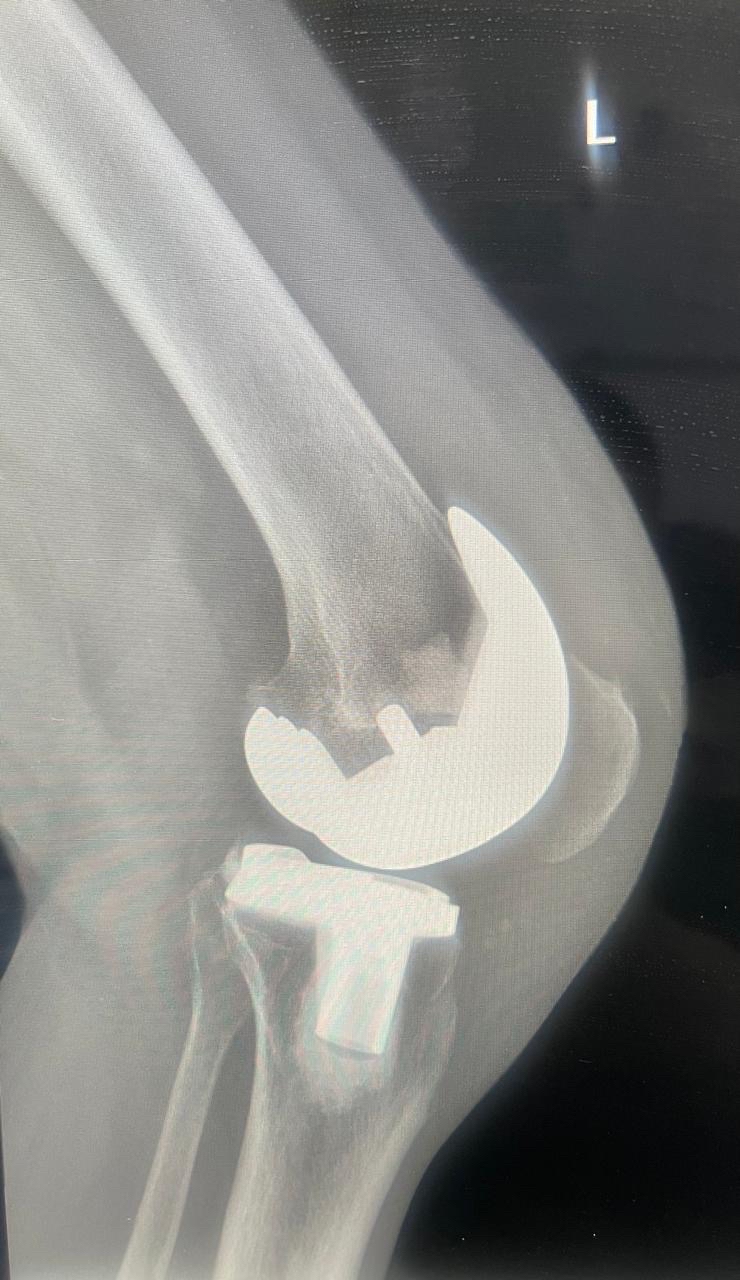

أعلن مستشفى القطيف المركزي إطلاق وحدة تخصصية لتبديل وترميم المفاصل، متوجاً انطلاقتها بإجراء 30 عملية جراحية ناجحة للركبة، لتعزيز كفاءة الرعاية الطبية وتطوير الخدمات وفق أحدث المعايير العالمية المعتمدة.

وأوضح المستشفى التابع لتجمع الشرقية الصحي، أن الوحدة الجديدة انضمت رسمياً للوحدات التخصصية بقسم العظام، مبيناً أن نجاح العمليات الثلاثين يعكس جاهزية الكوادر الطبية وتوفر التقنيات المتقدمة.

وبيّنت الجهات الطبية أن الوحدة تقدم منظومة رعاية متكاملة، تبدأ بتقييم وتشخيص دقيق لحالات تآكل المفاصل والإصابات المزمنة، وصولاً للتدخلات الجراحية المبتكرة.